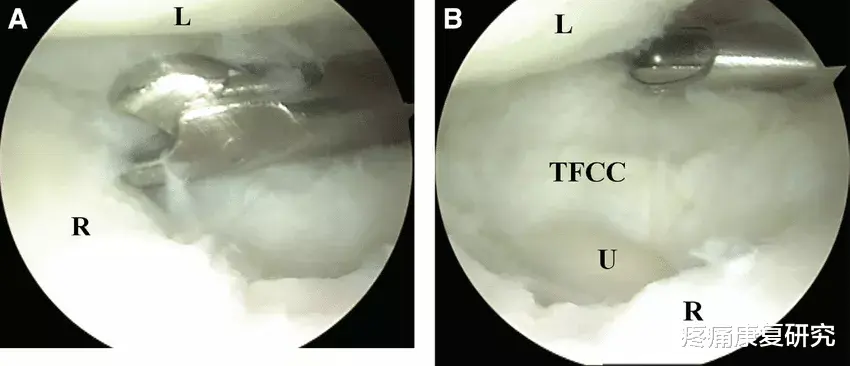

三角纤维软骨复合体(TFCC)是由一群纤维软骨与韧带组成的结构 , 位于腕关节内的尺侧(有小指的一侧) 。

- 它会帮助稳定桡尺远端关节(DRUJ)

- 为尺侧腕骨组织提供稳定度

- 能够吸收手腕20%的纵向冲击力

有些TFCC撕裂较小 , 稳定 , 可以通过保守治疗治愈 。 而另外一些TFCC撕裂较大 , 不稳定 , 可能需要手术干预 。